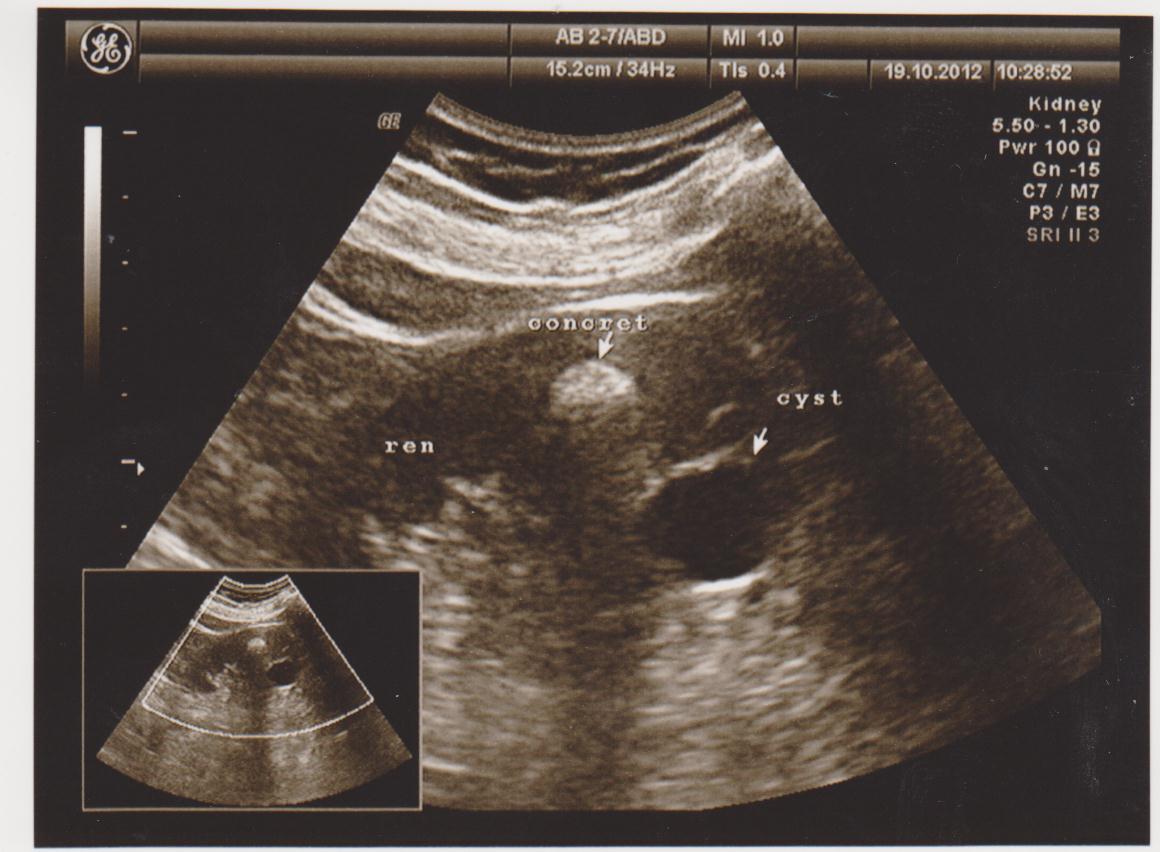

Частые болезни: кисты, новообразования (ангиомиолипомы, гемангиомы, фибромы…), конкременты (камни), расширение мочевых путей (расширение лоханки или чашечек — пиелоэктазия, гидронефроз), хроническое воспаление (пиелонефрит), смещение почек (опущение — нефроптоз, нахождение в нетипичном месте — дистопии), удвоение почки, рак почки…

Ниже я привел пару УЗИ снимков из практики, все они есть в галерее УЗИ на сайте, смотрите и не пугайтесь: